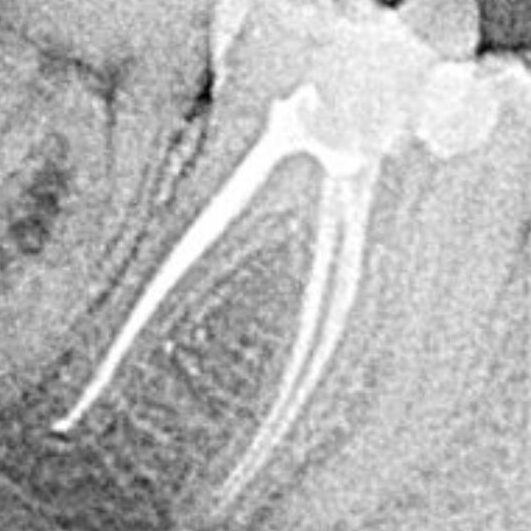

☞ цифровий прицільний та панорамний знімки,

☞ перевірка наявності карієсу, тріщин,стертості та ін.,